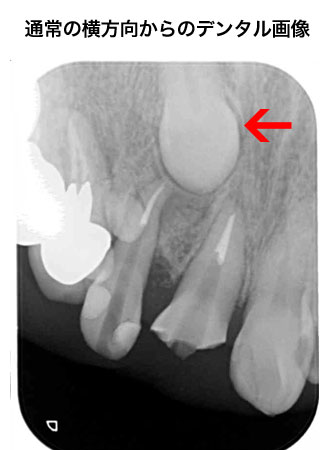

デジタルレントゲン

当院ではあえてCTを採用せず、デジタルパノラマ・セファロレントゲンを採用しました。

CTの1回あたりの撮影の際の被爆量は250μSであるのに対し、デジタルパノラマ・セファロレントゲンは10分の1の25μSvであるからです。

(デジタルパノラマ・デンタルレントゲンは10μS)

被爆量の低減について、医療側の努力が必要であるからです。

3次元的なレントゲンの検査方法として、下記の様な物があります。

方向の異なる画像を読影して診断する事が可能です。